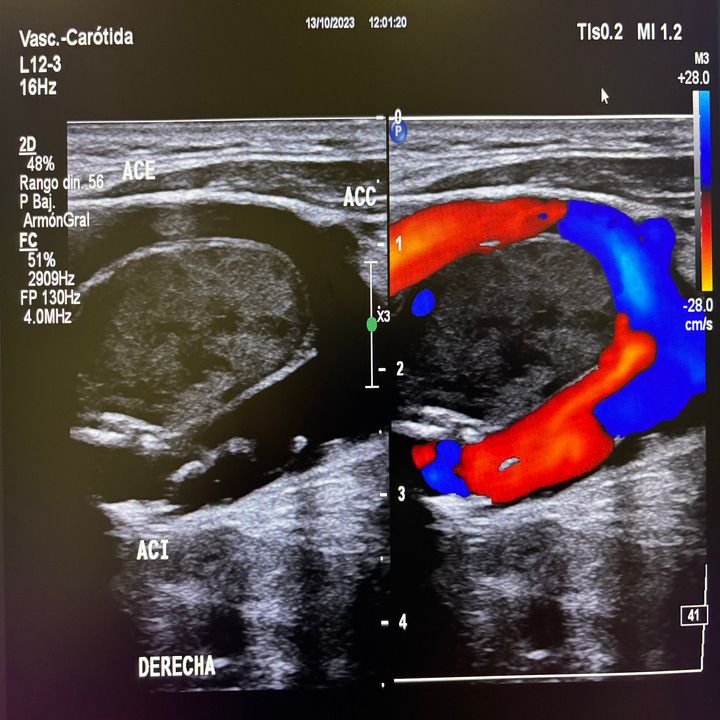

• Diagnóstico vascular no invasivo